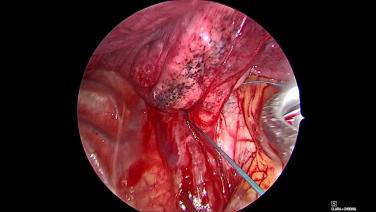

Thorascopic Lobectomy - Dissect Out & Encircle Pulmonary Artery